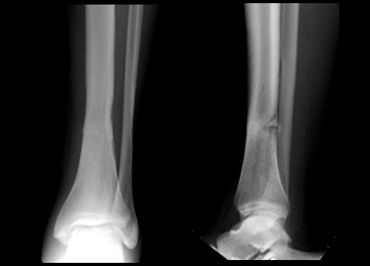

Stress fracture of the lower tibia. Stress fracture of the lower tibia.

On the left a 50-year old male, who led a sendentary life.

He participated in a 10-mile walking contest without any training beforehand.

Gradually pain developed in the lower leg and in the end he was unable to walk any further.

The x-rays show a stress fracture of the lower tibia.

Doing too much too soon is a common cause of stress fractures.